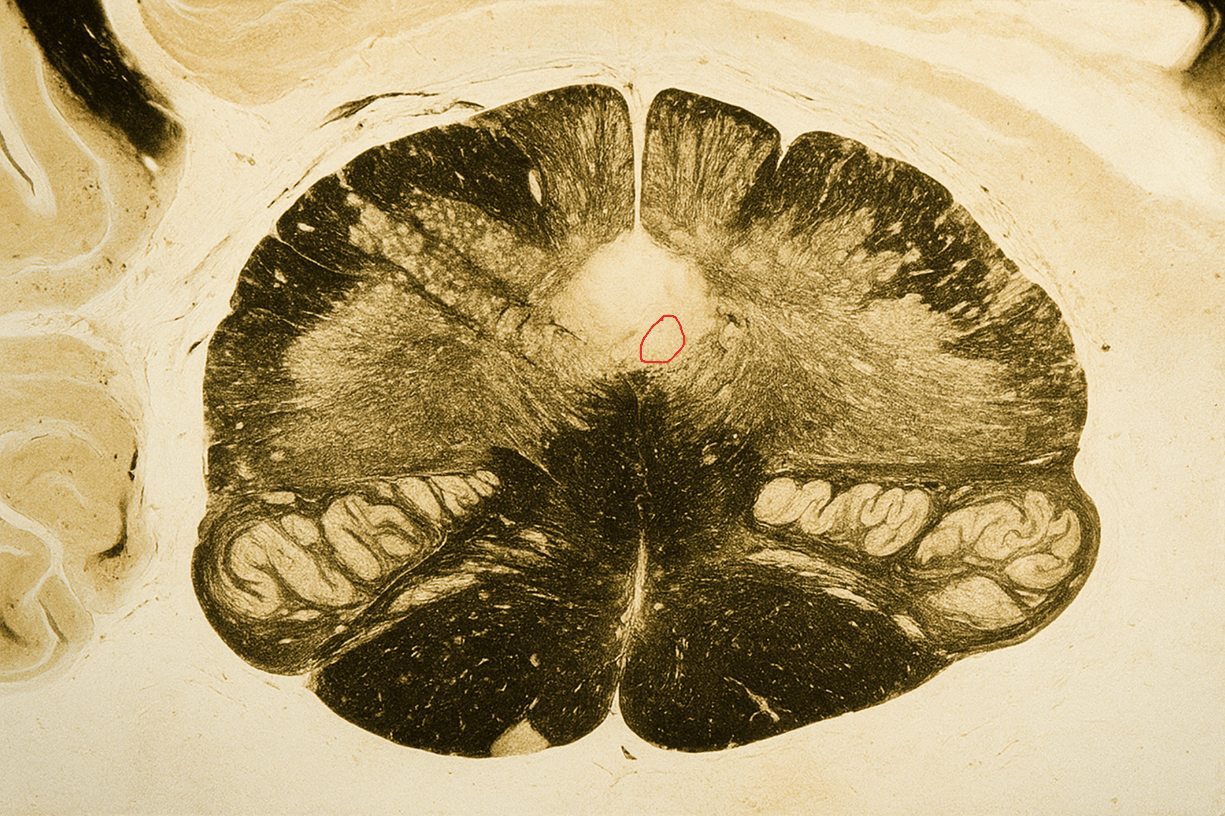

Identify the circled nucleus and state whether a lesion here would produce a contralateral or ipsilateral deficit.

Answers: Hypoglossal nucleus and ipsilateral deficit

This is one of the hypoglossal nuclei, whose lesion causes ipsilateral tongue weakness and deviation toward the side of the lesion due to loss of lower motor neuron input to tongue muscles.